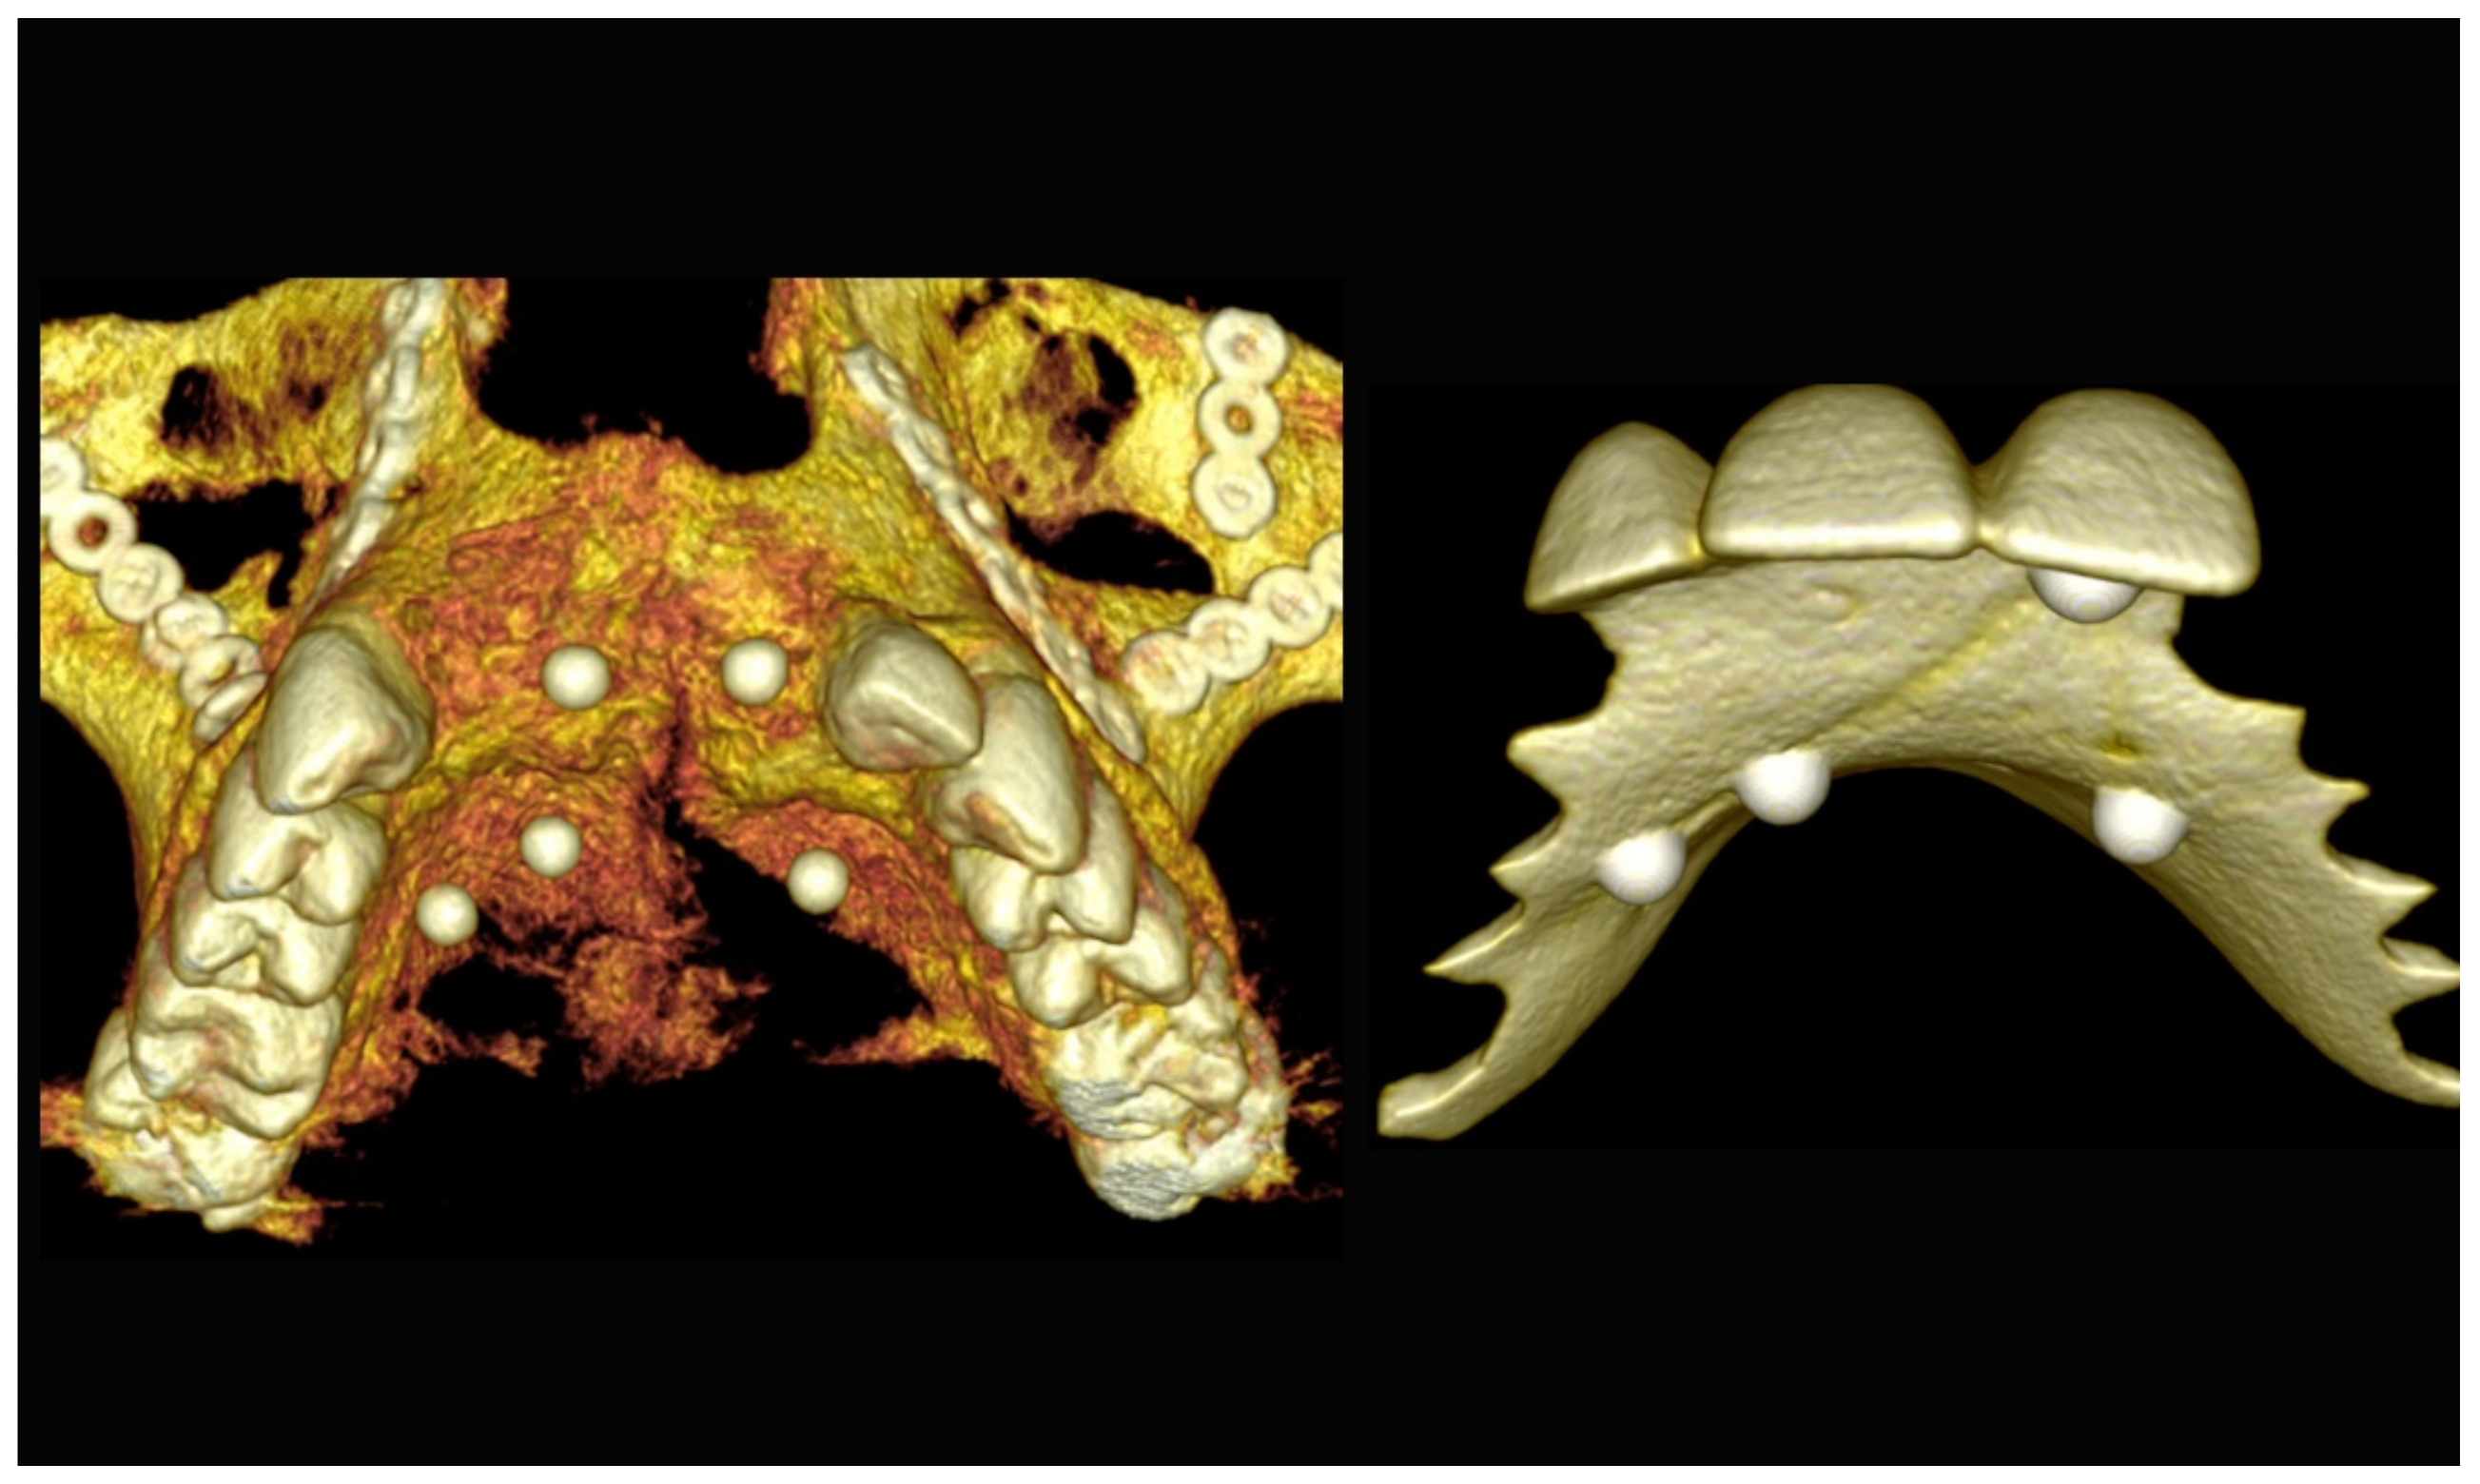

6.2.3. Image Segmentation and Virtual Planning:

The number, the length, the diameter and the placement of computational virtual implants were determined with respect to the design of the final prosthesis the available residual bone volume and the anatomical limitations according to the previously described technical procedure (Figure 16, Figure 17, Figure 18, Figure 19, Figure 20 and Figure 21).

Figure 16.

Three-dimensional (3D) CBCT scan images with the patient wearing the planned prosthesis.

Figure 17.

Three-dimensional (3D) CBCT scan images of the prosthesis equipped with integrated radiopaque reference spheres scanned separately.

Figure 18.

Three-dimensional (3D) planning of the number, the diameter and the axis of dental implants with respect to the design of the final virtual maxillary prosthesis.

Figure 19.